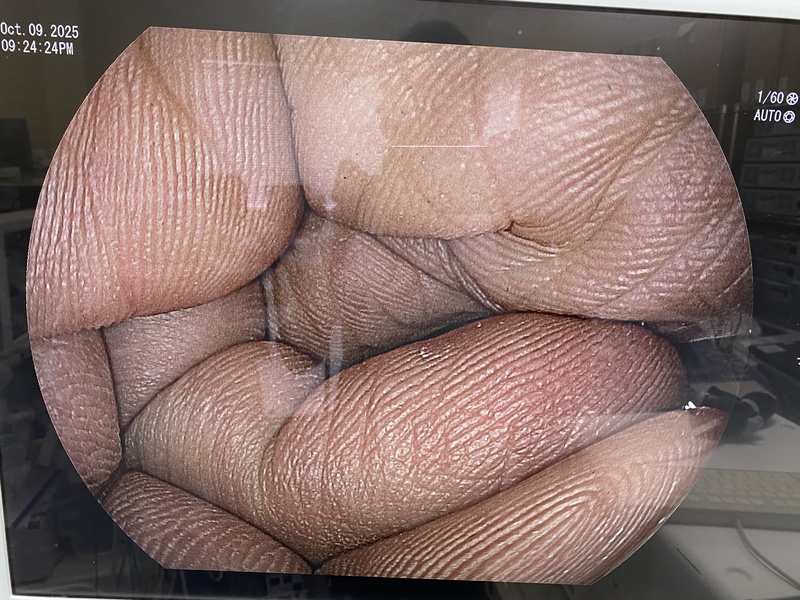

- detail Video Gastroscope / 16684 / EG-590WR